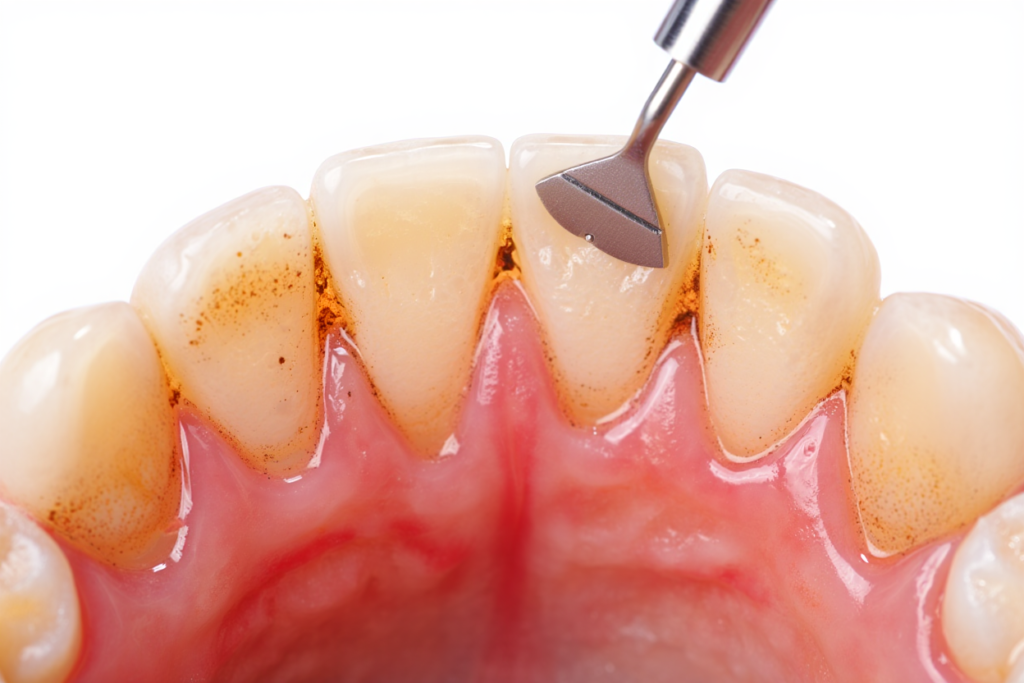

🦠 Cao răng tích tụ lâu ngày

👉 90% trường hợp viêm nha chu bắt nguồn từ cao răng không được làm sạch định kỳ.

✔️ Lấy cao răng siêu âm

🔹 Bước 2: Lấy cao răng và mảng bám